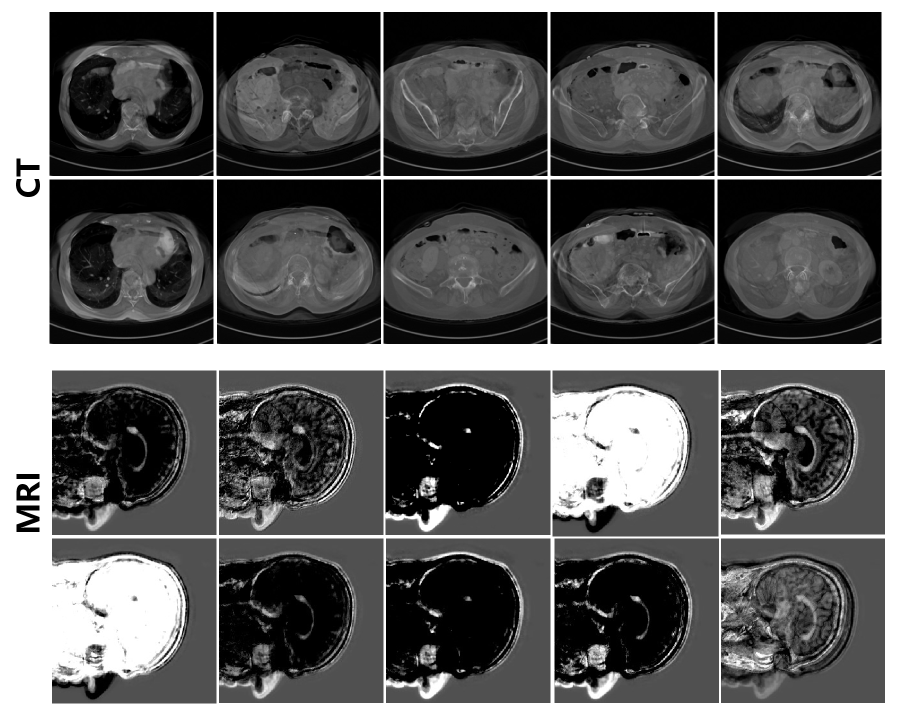

Visualization of the Distilled Data. We present the synthetic data distilled by our method. When NRI = 10 and IPP = 1, the synthesized samples for both CT and MRI modalities are shown in Fig. 7. It can be observed that the synthetic data integrate anatomical characteristics from multiple images, while still preserving variations across different patients, thereby aiding in the preservation of patient privacy.

Refer to caption

Figure 7: Distillation results of our methods. Each image represents the synthetic data of a patient.

Visualization of the Distillation Process. We visualize the synthetic images across different training iterations to illustrate their evolution. Under the setting of NRI = 10 and IPP = 1, the distilled results at different iterations are shown in Fig. 8. As observed, the synthetic images evolve from their initial state and converge, demonstrating that our method effectively injects patient-specific information into the distilled data. Notably, throughout the entire process, no patient data is explicitly transmitted to the user, thereby preserving privacy. Additional privacy-related experiments can be found in our Appendix.

Figure 8: Visualization of the distillation process.